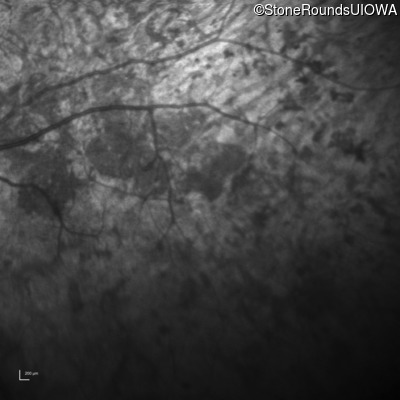

Infrared Fundus Photograph - Left - Light Perception

Exemplar

Fundus Photography - Right - Light Perception

Fundus Montage - Right - Light Perception